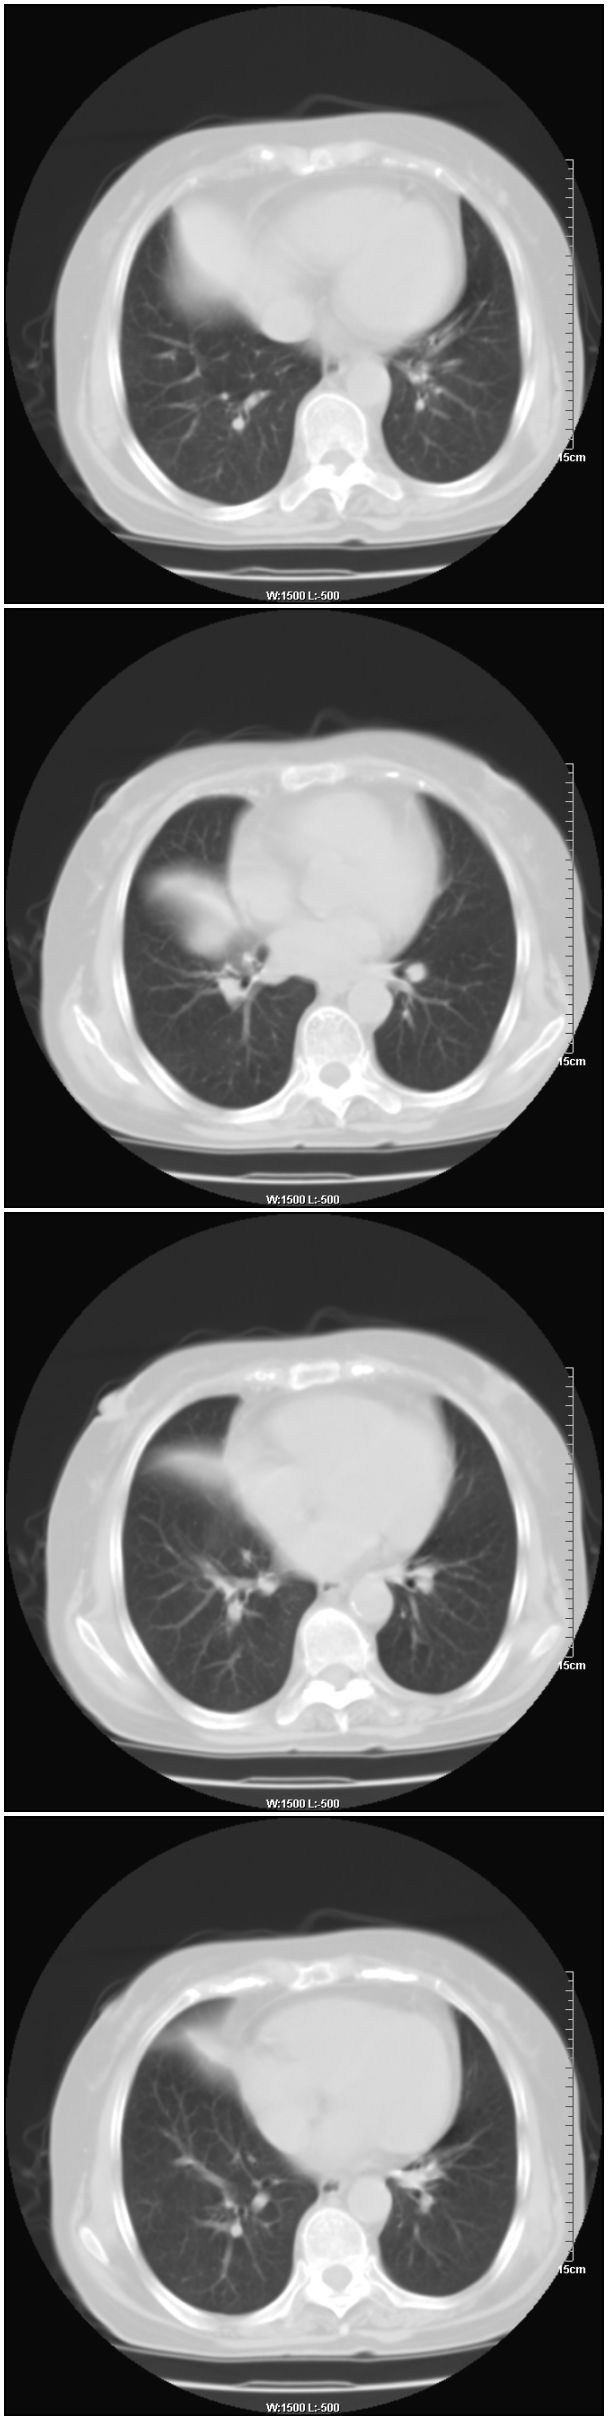

女性,78岁。术前体检发现肺部病变,看看还有什么问题?肺病变是什么性质?

支持!右肺中叶中心型肺癌!右侧乳腺内上象限结节,建议薄扫

乳腺病变在右侧,右肺门区新生物伴右中叶阻塞性肺炎、部分部张

右肺中叶不规则肿块,管腔阻塞,心包内少量积液,支持右肺中心型肺癌。

1.右侧乳腺病变。

2.右肺病变,考虑:肺癌可能性大。(病变边缘光滑,硬化性血管瘤或其他良性肿瘤待除外)

右侧乳腺内上象限结节影,边缘模糊,右肺病变相邻支气管内见软组织密度影及斑点样钙化灶,考虑肺癌可能性大,建议结合纤支镜检查。

右肺中央型肺癌伴中叶肺不张。